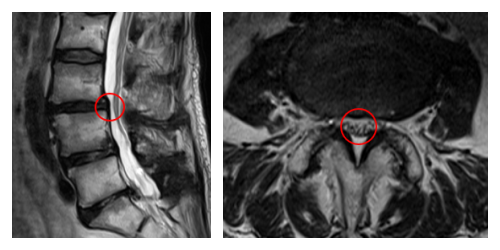

┃検査・診断

赤い枠で囲われている部分(L3/4 )に狭窄を認めました。